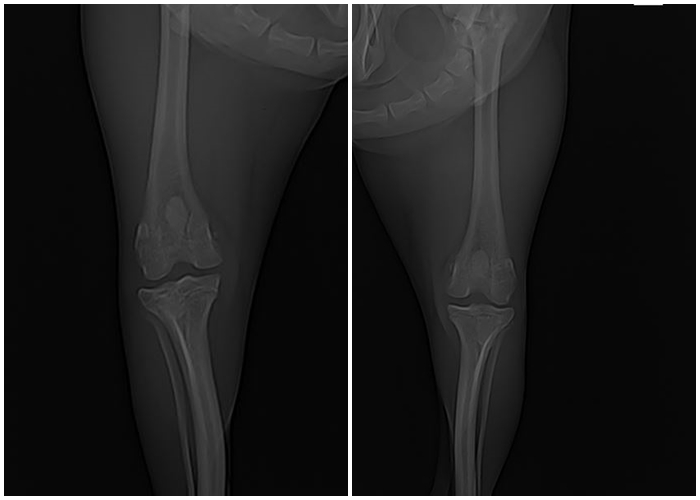

수술 후 방사선 사진에서는 슬개골이 제 위치에 안정적으로 자리잡은 것이 확인되었습니다.

수술 후 방사선 검사 사진 / 출처: 라온동물메디컬센터